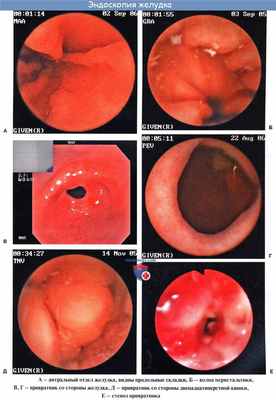

Эндоскопия желудка

Непосредственное наблюдение за полостью желудка больного возможно также с помощью особого оптического прибора гастроскопа, вводимого через пищевод в желудок и позволяющего производить осмотр желудка изнутри (гастроскопия).

Гастроскопически определяются складки слизистой оболочки, которые извиваются в различных направлениях, напоминая рельеф мозговых извилин. В норме кровеносные сосуды не видны. Можно наблюдать движения желудка. Данные гастроскопии дополняют рентгеновское исследование и позволяют изучить более тонкие детали строения слизистой оболочки желудка.